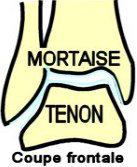

CHEVILLE - Articulation TALO-CRURALE

(old. tibio-péronéo-astragalienne)

Généralités

Véritable carrefour entre le

corps (axe vertical) et le sol (axe horizontal), elle unit le

tibia

et la

fibula (

old. péroné) au

talus

(

old. astragale). C'est une

articulation de type

trochléenne (1

ddl) qui est bridée latéralement par les malléoles interne et externe

ainsi que de puissants ligaments.

Surfaces

Articulaires

Surfaces

Articulaires

Elles s'encastrent l'une dans

l'autre à la façon d'un tenon et d'une mortaise.

La poulie du talus déborde largement (de 1/3) de la mortaise. L'axe de

rotation est oblique en DH et en ARR.

- Le tenon est constitué des 3 faces articulaires du talus (old.

astragale) : (face supérieure en forme de poulie dont la

gorge est oblique en AV et en DH, elle est convexe d'AV en ARR, et

répond à la surface inférieure du tibia. Elle est plus large en AV -

la face Interne est concave et répond à la face externe de la malléole

médiale - la face externe répond à la face interne de la malléole

latérale)

- L'axe médian de la mortaise est oblique en AV et en DH (valgus du

pied). la mortaise tibio-fibulaire possède 3 faces ou parois :

- face supérieure : c'est la face inférieure concave du pilon

tibial, plus large en AV, elle répond à la poulie du talus

- face interne : c'est la face externe de la malléole tibiale

(médiale), triangulaire à sommet postérieur qui s'articule avec la

face interne du talus

- face externe = c'est la facette articulaire de la malléole

fibulaire (latérale), triangulaire à sommet inférieur qui s'articule

avec la face externe du talus